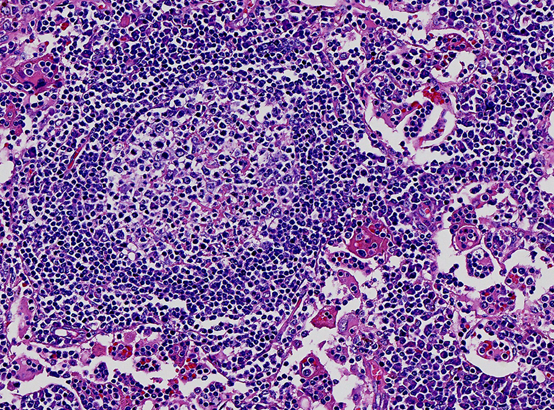

人体淋巴增生是多么的“绚丽多彩”